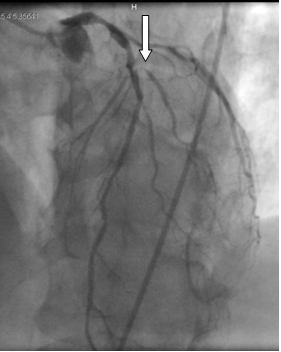

Хроническая окклюзия артерий: причины, симптомы и лечение